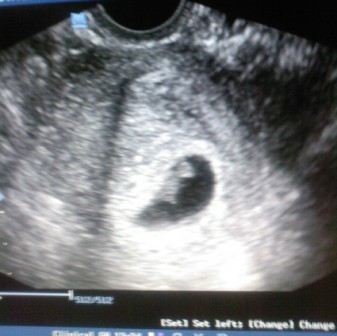

Sziasztok, csak gyors beszámoló, majd jövök a részletekkel. Nagy mázlink volt, hogy megUHzott egyik doki, aki amúgy nem tette volna, ha nincs ott a szülésznőm. Imádom azt a nőt!!! No szóval:

Petezsák: 35 mm

CRL: 10 mm

Szívhang kimutatható

Doki 6 hetesnek mondta, Bendus kisebb volt 6 hetesen, szerintem több annál... 7-8 körül lehet. Majd 2 hét múlva kb elmegyek a saját dokimhoz (Ő szabin volt).

Szülésznőmnek hála sikerült UH-ra jutnom, amúgy nem ment volna... szóval doki 6 hetesnek mondta, de én 7-nek gondolom a méretek alapján... itt még azért eléggé átlagosak szoktak lenni a méretek. 10 mm CRL elvileg 7 hét. Így a szülést dec. 1re dobja ki. :shock: